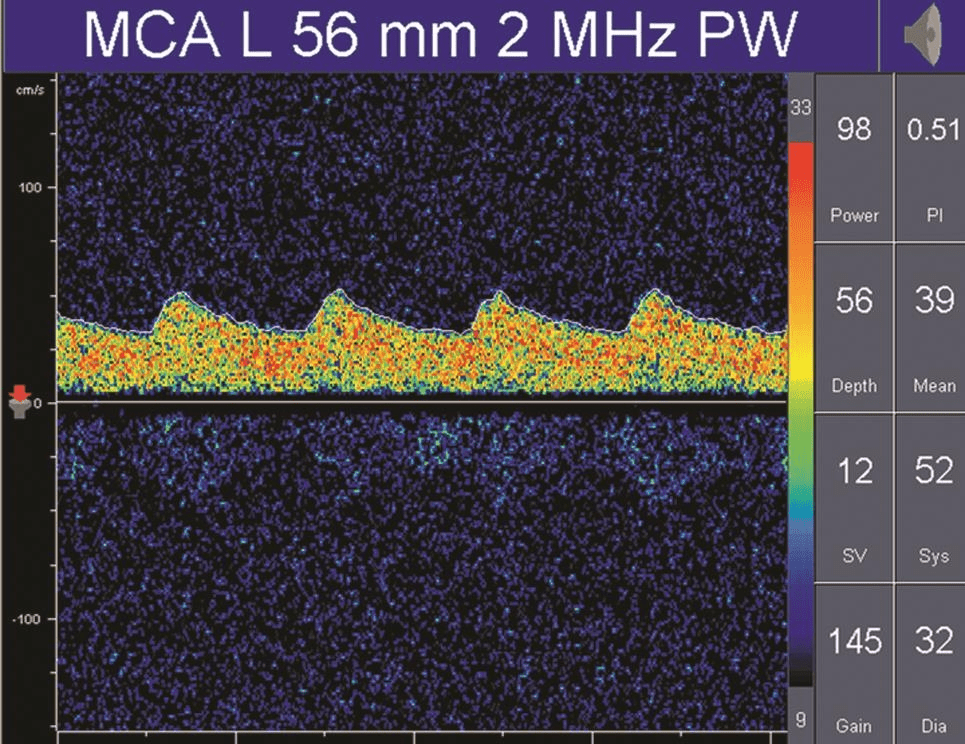

在病理情況下,低阻力頻譜可見于動靜脈畸形供血動脈、大動脈嚴(yán)重狹窄或閉塞后遠端灌注明顯不足的血管內(nèi)血流及開放的側(cè)支循環(huán)(詳情見下圖);

TCD多普勒TCD低阻力血流頻譜